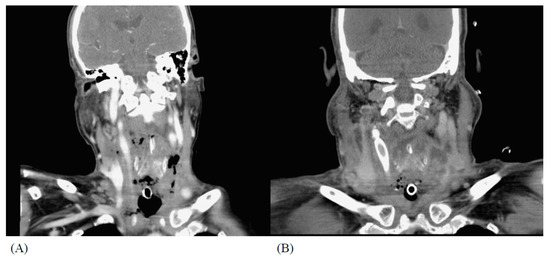

2.2. Case 2